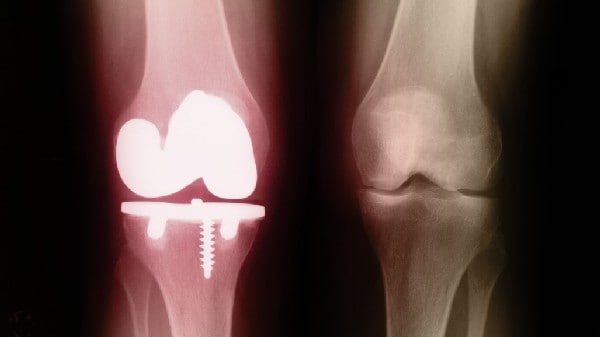

This process marks a significant departure from conventional fixation techniques that not only require subsequent surgical hardware removal but also may lead to complications such as infection, metallosis, and delayed union or nonunion of fractures. The bioinert materials, such as titanium and stainless steel, can sometimes impede natural healing due to their presence. Dissolvable glass, by contrast, offers a self-reinforcing trajectory toward full restoration, negating the need for secondary interventions.